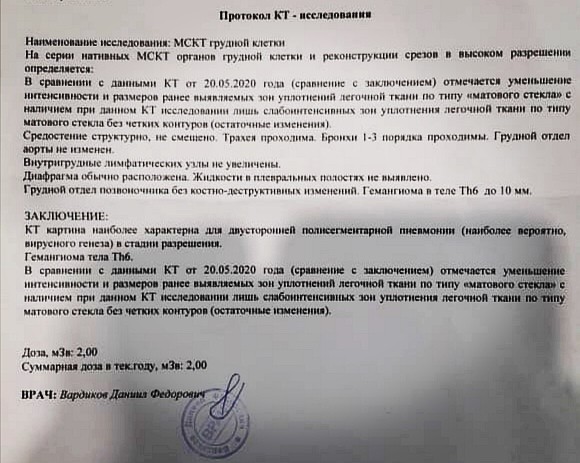

Фотографии и снимки КТ легких без контрастных веществ

Раздел: Визуальный дайджест